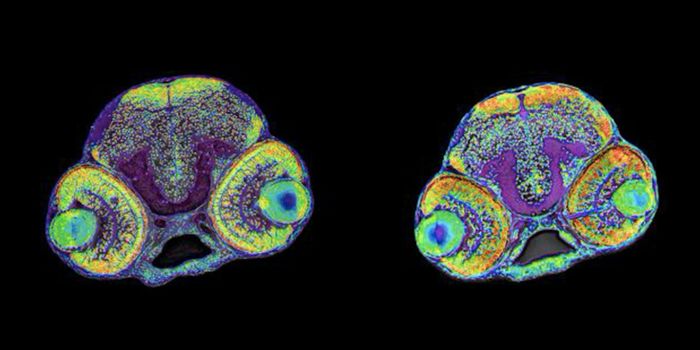

SEP 24, 2021Genetics & GenomicsKleefstra syndrome is a rare genetic disease caused by a mutation or deletion in one copy of a gene called EHMT1, which ...